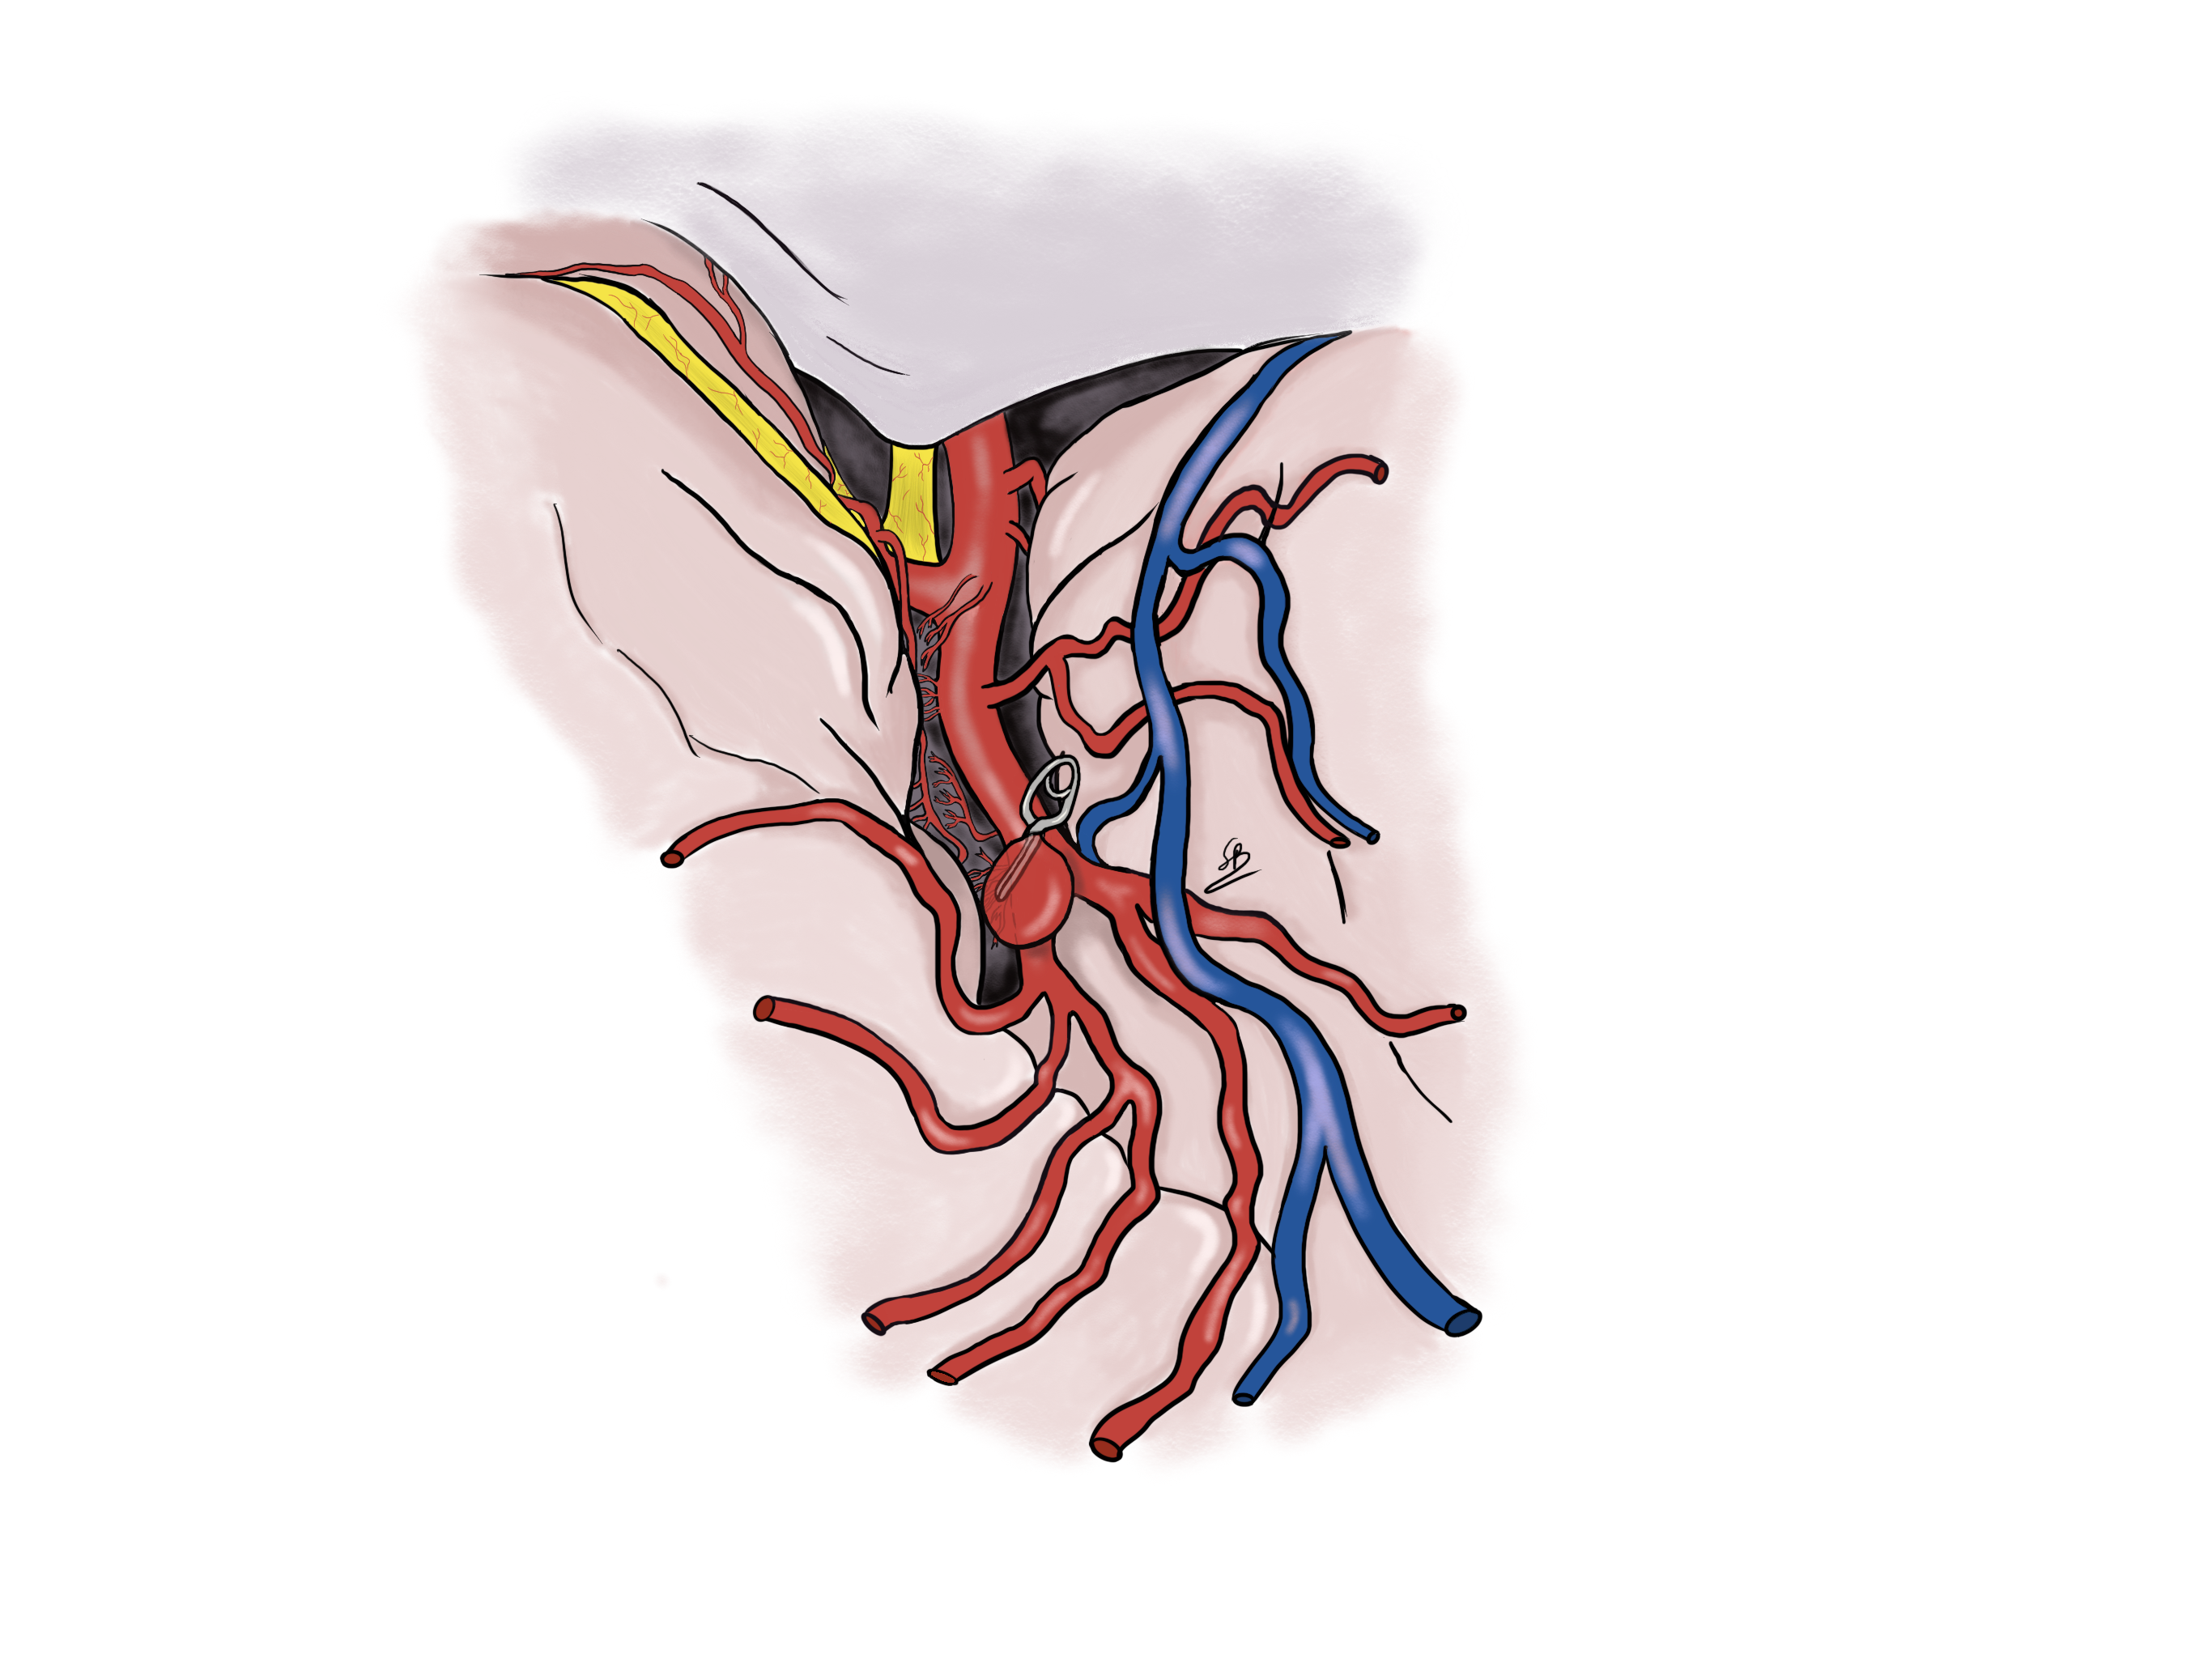

Aneurism clipping

Two different treatments to exclude the aneurysm from the arterial circulation are available: the microsurgical clipping and the endovascular coiling. Dr Robert and Dr Bonasia have an important experience in the aneurysmal clipping. They realized more than 200 surgeries for this pathology. This is a treatment they propose at Clinique La Source in Lausanne.